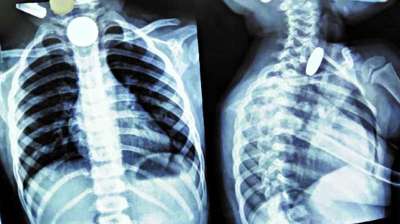

खिलौना नहीं सिक्का था! बच्चे ने निगले 5-10 रुपये के सिक्के, डॉक्टरों ने ऑपरेशन कर निकाले

24 Jul, 2025 04:09 PM IST | INTERNALNEWS.IN

दिल्ली : दिल्ली के एक सरकारी अस्पताल के डॉक्टरों ने 12 वर्षीय बच्चे की जान बचाई है। बच्चे ने पांच और दस रुपये के तीन सिक्के निगल लिए थे। सिक्के...